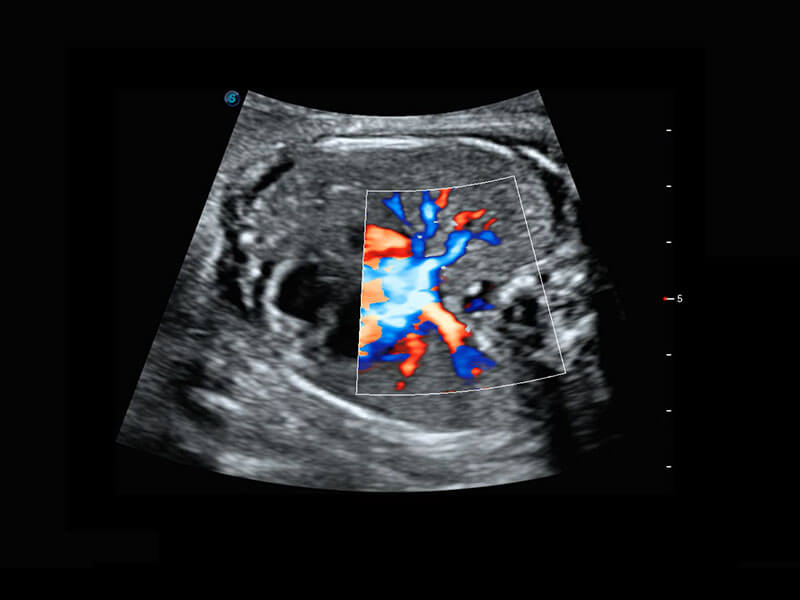

• 胎儿体循环

• 光影成像-孕囊